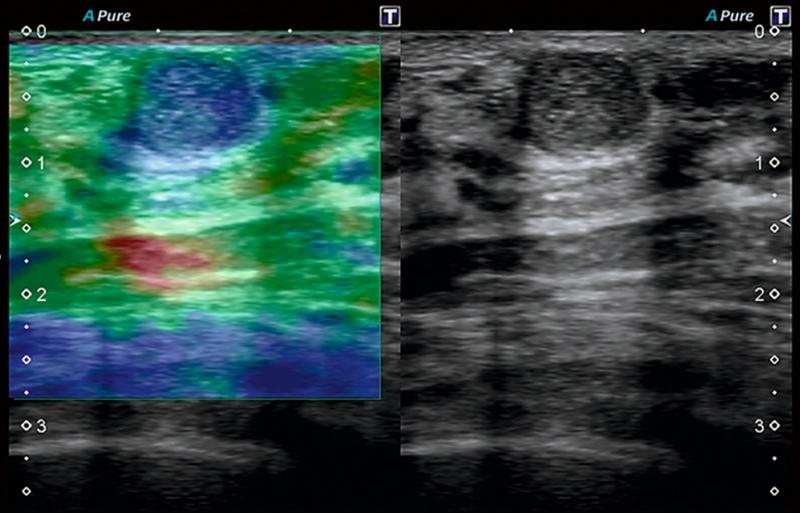

- УЗИ молочных желез. Ультразвуковое исследование — важное дополнение к маммографии, особенно у молодых женщин с плотной тканью железы. УЗИ позволяет детально оценить структуру образования, его кровоток. Для олеогранулемы характерно наличие образований различной эхогенности, часто с отсутствием кровотока внутри, что помогает в дифференциальной диагностике.

Эластография молочных желез: точная диагностика образований без биопсии

Обнаружено уплотнение в груди и вы боитесь биопсии? Узнайте все об эластографии молочных желез — современном методе УЗИ, который с высокой точностью определяет природу новообразований по их жесткости и помогает врачу принять решение о необходимости инвазивной процедуры.